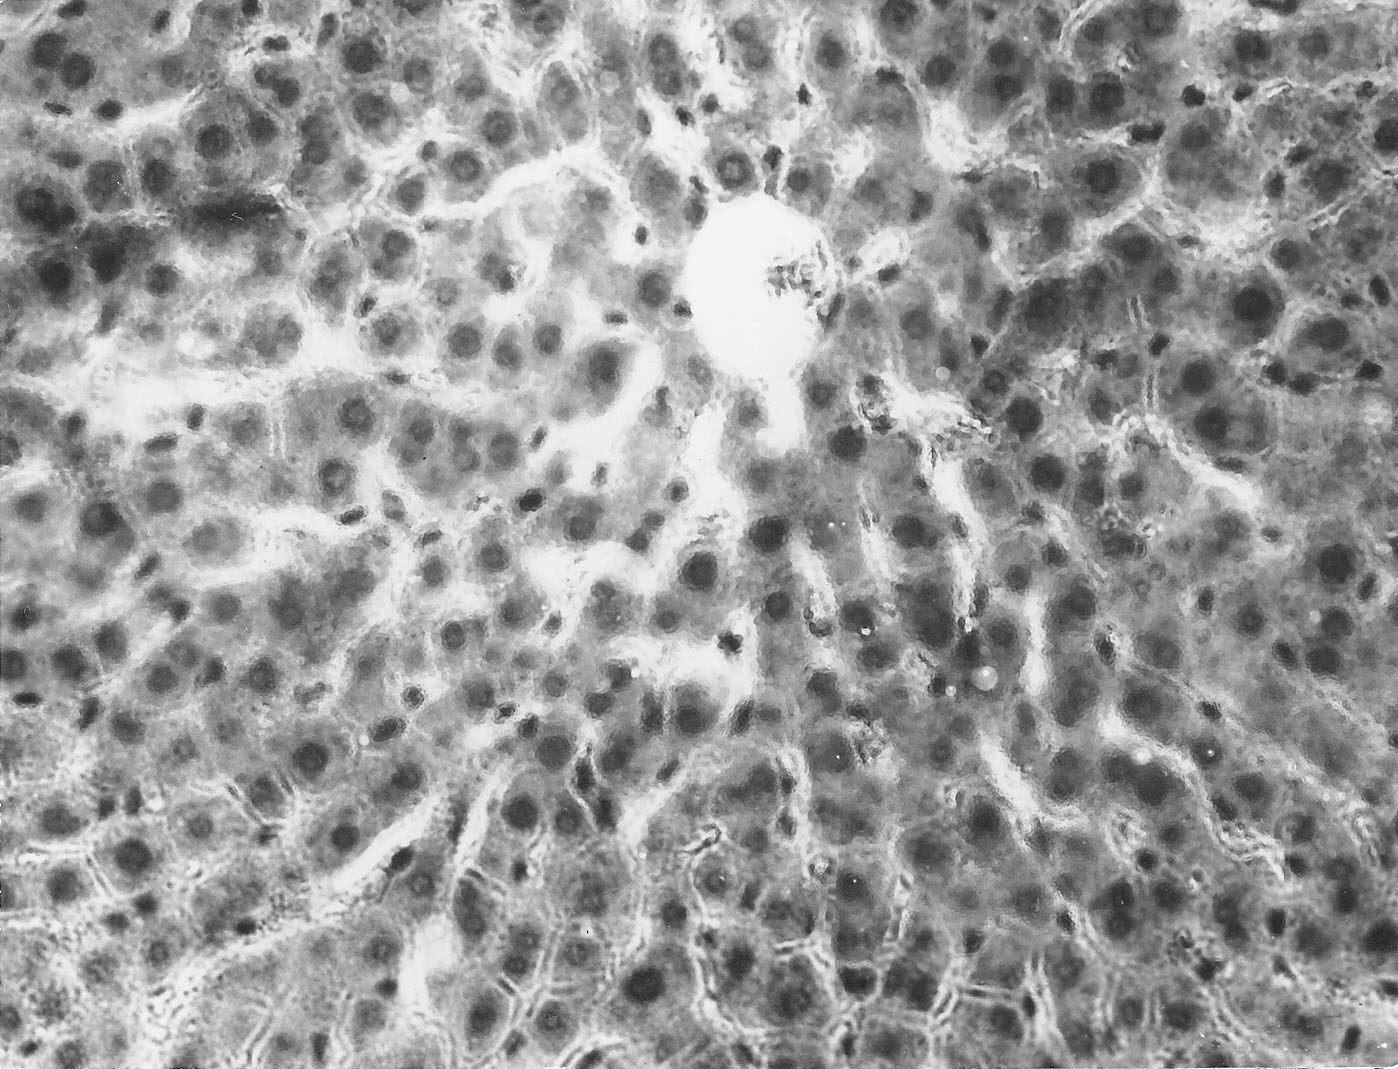

При исследовании внутренних органов крыс контрольной группы установлено, что печень имеет характерное дольчатое строение (рис.1). Печеночные дольки окружены соединительнотканной прослойкой. На периферии дольки располагаются триоды, состоящие из междолькового желчного протока, междольковых артерий и вен.

Гепатоциты формируют четко выраженные радиально лежащие балки, между которыми находятся умеренные кровенаполненные венозные синусы. Венозные синусоиды в центре долек формируют центральную вену с четко выраженным просветом. Гепатоциты многогранной формы, содержат 1 – 2 ядра, цитоплазма клеток равномерна окрашена.

Рисунок 1. Печень. Группа № 1 (контроль)

Печень имеет характерное дольчатое строение. Гепатоциты формируют четко выраженные, радиально лежащие балки. (Увел.400).